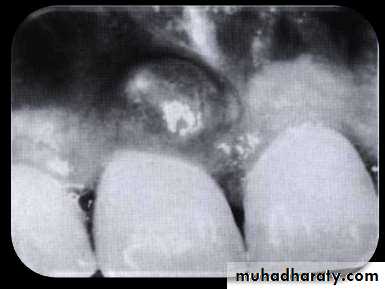

• Sinus

• Sinus orifice from a palatal periodontal abscess• Pinpoint orifice in the palate indicative of a sinus from a

• periodontal abscess.

• Probe extends into the abscess deep in the periodontium.

• Radiographic findings are sometimes helpful in differentiating between a periodontal and a periapical lesion

• Early acute periodontal and periapical abscesses present no radiographic changes.

• Ordinarily, a radiolucent area along the lateral surface of the root suggests the presence of a periodontal abscess, whereas apical rarefaction suggests a periapical abscess.